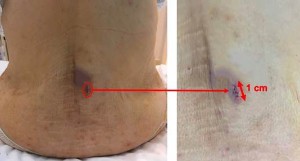

The endoscope is in Dr. Morgenstern’s hand (left). Note the minimal incision in

the skin of less than 1 cm in length and the absence of bleeding from the wound.

Postoperative images of a skin wound with a length of just 1 cm (red arrow). A small hematoma (blue in color) can be seen around the wound, which usually disappears within a few days after surgery.